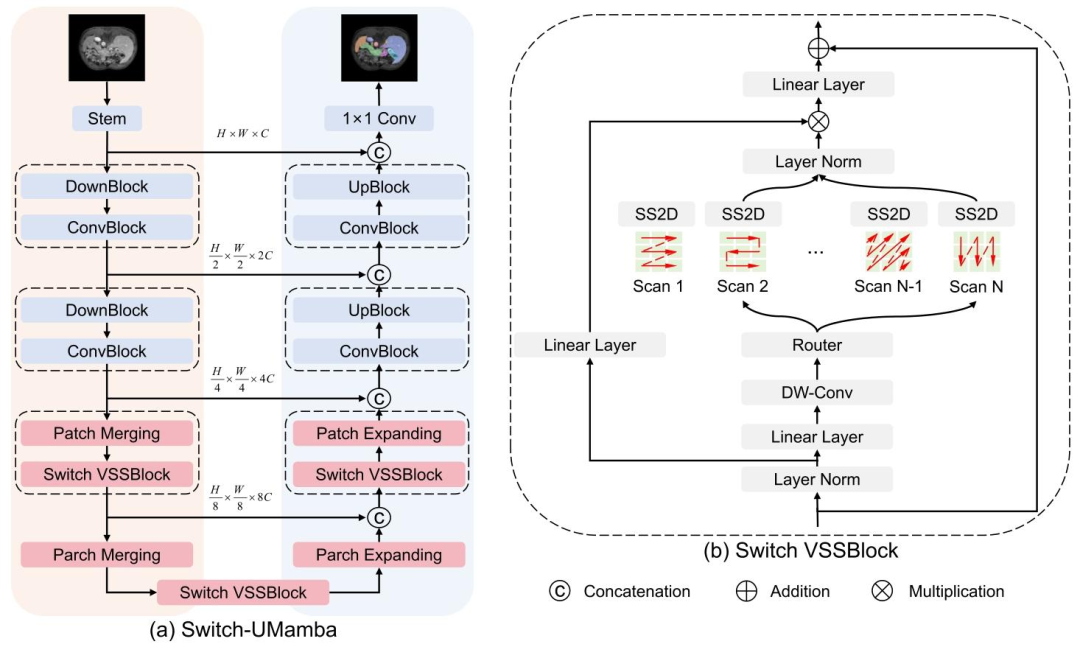

Fig. 2. The overall architecture of our proposed Switch-UMamba.

图2 所提Switch-UMamba模型的整体架构